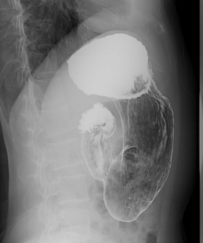

如果您最近吃了大量的柿子、山楂、黑枣、石榴等,又出现上述症状,请前往正规医院行钡餐、 CT 或胃镜检查。

上消化道钡餐检查